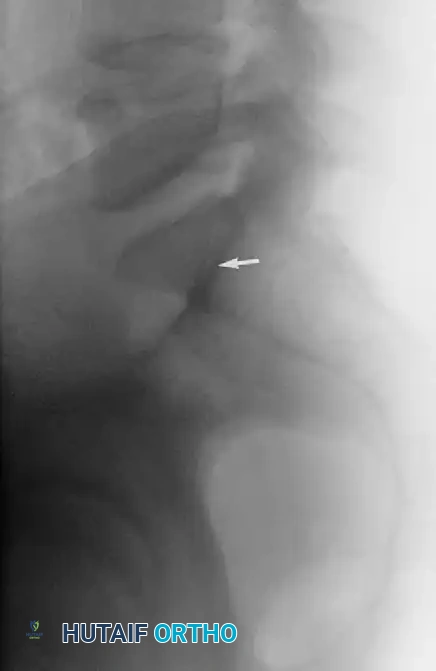

The sacral alar slope can be estimated on a true lateral fluoroscopic view of the sacrum by identifying the Iliac Cortical Density (ICD). The ICD demarcates the anterior cortical thickening of the iliac portion of the sacroiliac joint.

In the vast majority (approx. 94%) of non-dysplastic upper sacral segments, the ICD coincides perfectly with the alar slope, making it an invaluable radiographic landmark for determining the anterior border of the safe zone during surgery.

Image

The Iliac Cortical Density (ICD) identified on a lateral radiograph for estimation of the sacral alar slope.